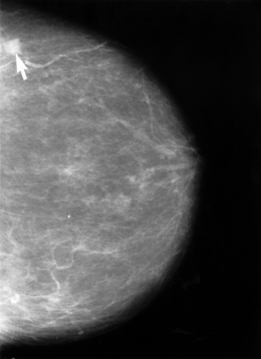

Молочная железа состоит из трёх типов тканей: железистой, фиброзной (соединительной) и жировой[3]. Относительная плотность органа определяется наследственными особенностями, гормональным статусом, возрастом и количеством беременностей. Рентгенографическое изображение позволяет различать эти ткани благодаря разнице в их плотности: более плотные железистая и фиброзная ткани выглядят светлыми участками, жировая — серыми различной интенсивности.

Информативность маммографии зависит от возраста и структуры молочной железы. В жировой ткани чувствительность метода приближается к 100 %, при плотных железах от 10 до 40 % случаев могут быть рентгенонегативными[4]. Метод выявляет около 75 % случаев рака у женщин 40-50 лет и до 90 % — у женщин 50-70 лет[4]. Специфичность достигает 95-97 %[22].

На маммограмме можно обнаружить образования от 2 мм в диаметре. До появления пальпаторных признаков может пройти 2-4 года. В типичной городской поликлинике за год маммографию проходят 500—1500 женщин скринингового возраста, из них 3-4 % нуждаются в дообследовании. Примерно в 1 % случаев выявляются рентгенологически достоверные признаки рака, включая минимальные опухоли размером до 10 мм.

Рак молочной железы обычно разделяют на инвазивную и неинвазивную формы. Неинвазивная карцинома представляет собой своеобразную форму процесса, обладающую потенциальными возможностями к инвазии. Она редко метастазирует в силу особенностей своей биологии. Инвазивный рак, предположительно возникающий в конечном отделе дольково-протоковой единицы, прогностически значительно хуже. На рентгенограммах рак молочной железы визуализируется как образование с конгломератами кальцификатов и неровными краями[33]. Окончательная оценка процесса во всех случаях зависит от морфологического исследования.

Система BI-RADS включает оценку плотности молочных желёз, обозначаемую латинскими буквами от A до D. Плотность железистой ткани влияет на выявляемость патологических образований, поскольку как нормальная, так и патологическая железистая ткань выглядят светлыми на маммограммах. Тип A обозначает молочную железу, преимущественно представленную жировой тканью. Тип B указывает на молочную железу, в основном представленную жировой тканью с отдельными участками фиброзной и железистой тканей. Тип C характеризует молочную железу, представленную как жировой, так и фиброзной и железистой тканями в значительных пропорциях. Тип D обозначает молочную железу, полностью представленную фиброзной и железистой тканями. Высокая плотность железистой ткани затрудняет обнаружение патологических образований и незначительно повышает риск развития рака молочной железы[39][40].